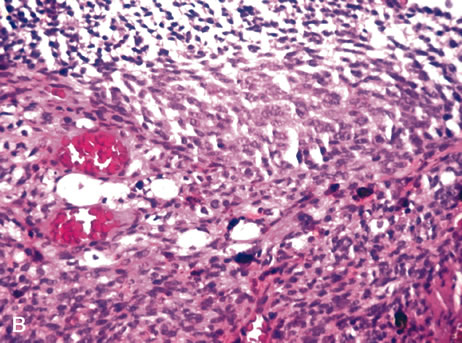

Three histologic patterns of granulomatous inflammation may be seen: diffuse, discrete, and zonal. In diffuse granulomatous inflammation, the epithelioid histiocytes are scattered throughout the involved uveal tissue (Fig. 19). There may be an accompanying background of lymphocytes and plasma cells. Discrete granulomatous inflammation reveals well-circumscribed areas of epithelioid histiocytes (Fig. 20). Zonal granulomatous inflammation consists of a central zone of necrosis and/or polymorphonuclear leukocytes surrounded by epithelioid histiocytes, which is in turn surrounded by a zone of non-granulomatous inflammation consisting of granulation tissue, lymphocytes and plasma cells (Fig. 21).

Fig. 21. Tuberculous choroiditis. A zonal granulomatous inflammation is present. Central area shows necrosis. (Hemotoxylin-eosin ×65.)

Diffuse granulomatous inflammation is typically seen in sympathetic ophthalmia and Vogt-Koyanagi-Harada (VKH) disease. Sympathetic ophthalmia has classically been described as an intraocular inflammatory response in the non-traumatized fellow eye following penetrating injury to the contralateral eye. The disorder is characterized by waxing and waning episodes of chronic inflammation; untreated, it may lead to blindness in both eyes. The patient may present with mild pain, photophobia, and vision loss. The exciting eye (previously traumatized) may demonstrate decreased vision and increased photophobia. Both eyes may reveal ciliary injection and vitritis.The exciting eye may develop keratic precipitates. The sympathizing eye may demonstrate mild uveitis and KPs on the endothelium. Posterior segment findings include papillitis, Dalen-Fuchs nodules (yellow-white lesions beneath the RPE), choroidal granulomas, and exudative retinal detachments. Histologically, both the traumatized and sympathizing eyes show diffuse granulomatous inflammation made up of nests of epithelioid cells and giant cells mixed with lymphocytes. This inflammation does not extend to involve the choriocapillaris. Dalen-Fuchs nodules are composed of nodular clusters of epithelioid cells lying between the RPE and Bruch's membrane (Fig. 22). Sympathetic ophthalmia represents an autoimmune process that may be related to an altered T-cell response to uveal antigens or other intraocular proteins.120–124